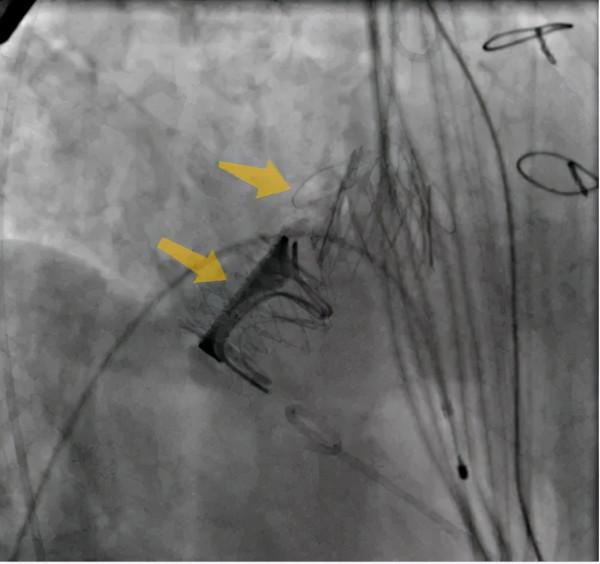

首先,鄭寶石團隊經左前外側胸部小切口,顯露心尖,在荷包線內穿刺,經DSA(數字減影技術)引導下,按預定順序,在主動脈瓣位置成功置入27號J-Valve介入瓣。

接著,黃凱調整導絲方向進入二尖瓣,用球囊預擴狹窄的生物瓣,再置入25號倒裝的J-Valve介入瓣,球囊後擴,完成瓣中瓣置入。

吳棘主任開展食道超聲和DSA實時評估,兩個介入瓣膜位置良好,啟閉正常,跨瓣壓差明顯減輕,無瓣周漏,這標誌著手術成功完成。術後,農姥姥一般情況穩定。